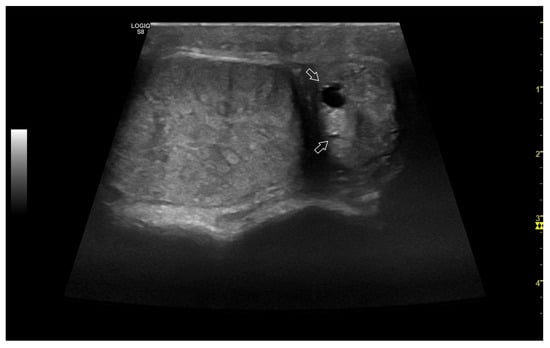

3.4.1. Intratesticular Diseases

3.4.2. Extratesticular Diseases